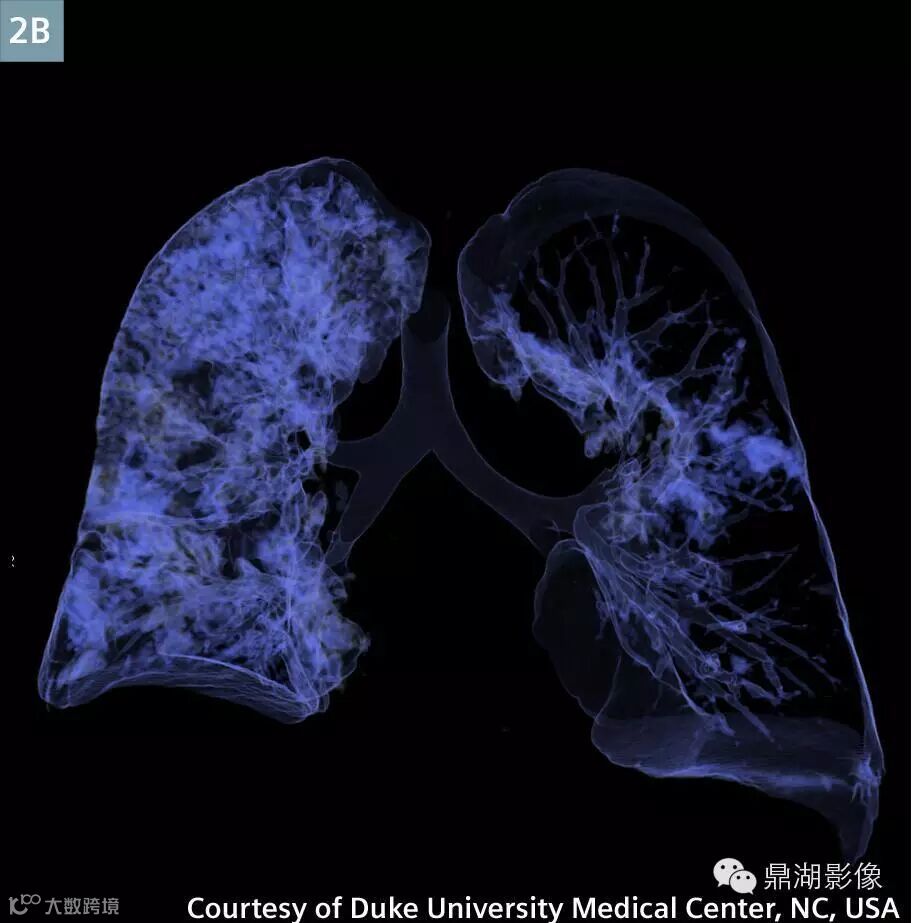

Coronal contrast-enhanced MPR (Fig. 2A) and VRT (Fig. 2B) image at the level of the pulmonary hila: Extensive right lung consolidative opacities represent pulmonary infarction.

肺动脉CTA显示新的多发性肺栓塞和右动脉完全闭塞(图1)。左下叶肺动脉和静脉灌注一直持续(图3)。存在广泛右肺动脉梗塞(图2)。上腔静脉,右心房,右心室充满造影剂,造影剂回流进入肝静脉和下腔静脉(图5A)。主肺动脉CT值衰减大于250亨氏单位,这可以让医生确定扫描的诊断质量。ECMO系统和主动脉的分支未显影,体现了良好的团注时间(图4)。